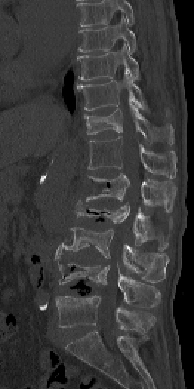

【術前】

CT検査で関節突起部に腰椎分離症を認めています。若年者の腰痛の原因となります。

【術後】

CT検査で関節突起部の骨移植を伴う分離部修復術を施行し骨癒合が得られています。